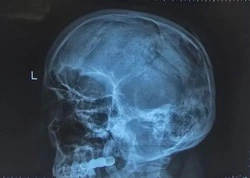

В областном реабилитационном центре участникам боевых действий оказали медицинскую помощь и помогли восстановить работу поврежденных органов. Многие из них вернулись на передовую, а некоторые по состоянию здоровья больше не могут продолжать службу с оружием в руках. Независимо от их дальнейших планов, с каждым из пациентов, получивших ранение, занимается команда специалистов. Об этом сообщили в пресс-службе правительства Сахалинской области.